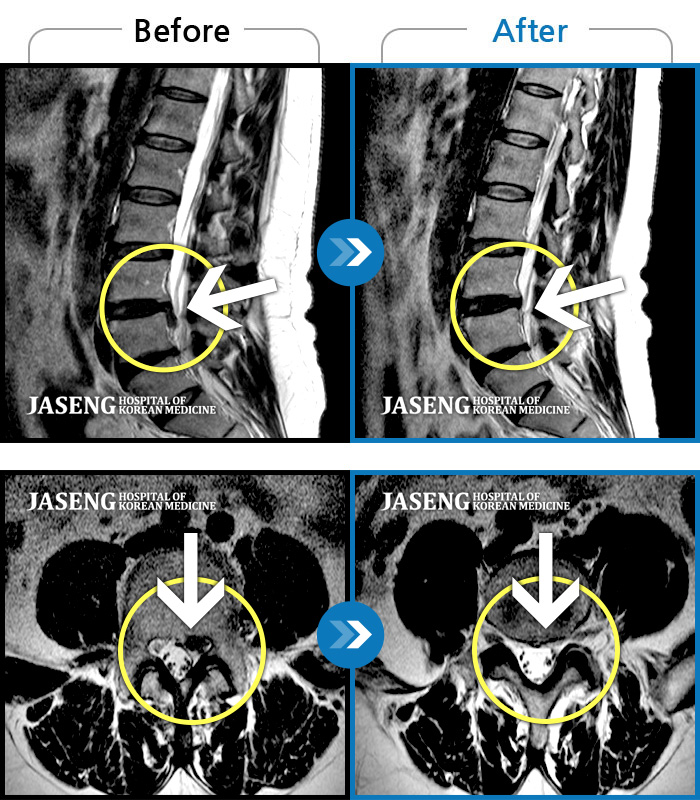

허리디스크

해운대 · 김상돈 원장

아래쪽 허리와 우측 골반에 통증이 있었습니다.

촬영시기

2019.08.26 ~ 2025.08.09

2025.08.14

조회수 262